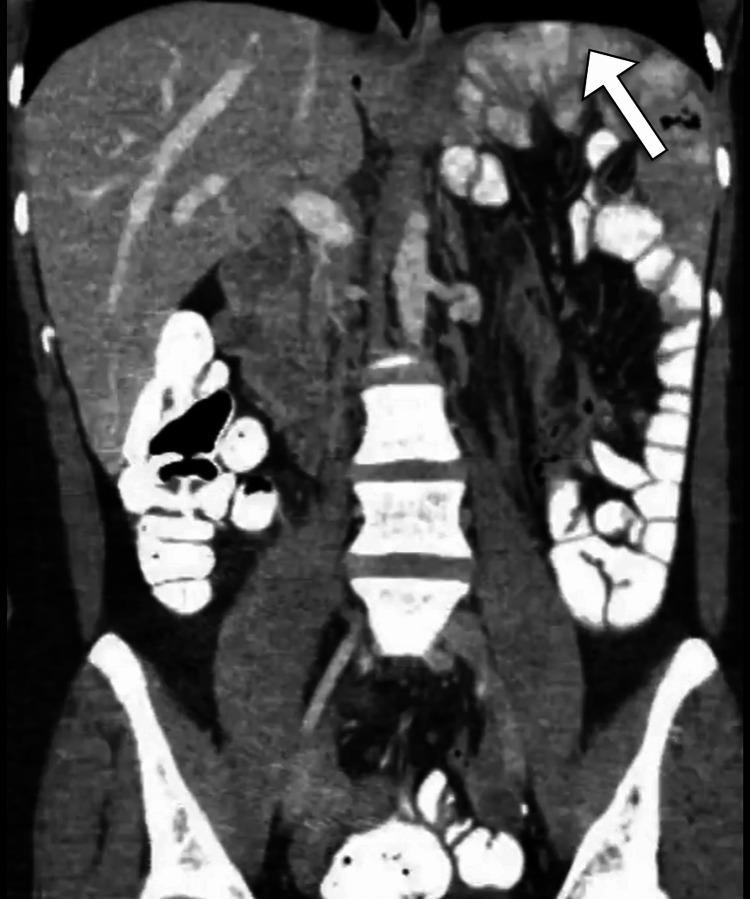

The spleen is typically located in the left upper quadrant and is held in position by the suspensory ligaments, which include the gastrosplenic ligament, the splenorenal ligament, and the phrenicocolic ligament. Abnormalities within these ligaments result in the mobility of the spleen, so it may be located in the pelvis or iliac region, which is termed a wandering spleen. We present a case of a middle-aged man who presented to the emergency department with generalized abdominal pain and diffuse guarding and tenderness. The patient had a previous history of peptic ulcer disease and multiple emergency department visits for gastritis. Given the assumed diagnosis of perforated viscus, the patient underwent a computed tomography scan that demonstrated the absence of the spleen in its usual location and showed an ectopic pelvic spleen. The patient underwent successful surgical treatment with splenopexy. The wandering spleen is a rare medical condition that presents a clinical diagnostic challenge and requires a high index of suspicion. Despite its rarity, the wandering spleen should be considered in patients with recurrent abdominal pain.

脾脏通常位于左上腹,由悬韧带固定其位置,悬韧带包括胃脾韧带、脾肾韧带和膈结肠韧带。这些韧带出现异常会导致脾脏活动,因此脾脏可能位于盆腔或髂区,这种情况被称为游走脾。我们报告一例中年男性病例,该患者因全腹疼痛、弥漫性腹肌紧张和压痛就诊于急诊科。患者既往有消化性溃疡病史,曾多次因胃炎就诊于急诊科。鉴于初步诊断为脏器穿孔,患者接受了计算机断层扫描,结果显示脾脏不在其正常位置,而是位于盆腔异位。患者接受了脾固定术,手术成功。游走脾是一种罕见的病症,会带来临床诊断挑战,需要高度怀疑指数。尽管罕见,但对于反复腹痛的患者应考虑游走脾的可能性。